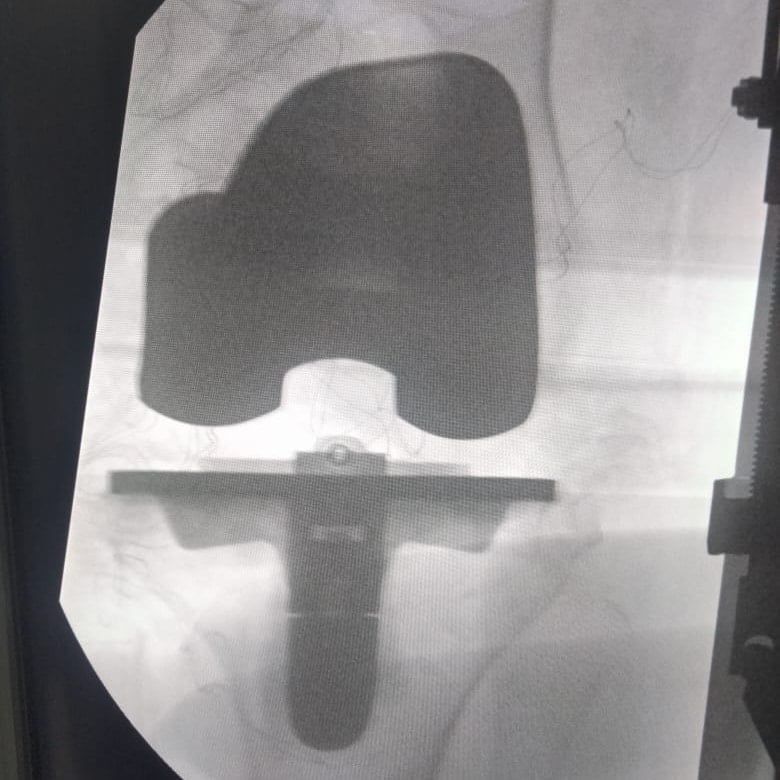

إنجاز جديد لقسم العظام بالمستشفىوكشف الدكتور كامل خالد مدير مستشفى قها التخصصي، أنه في إنجاز جديد لقسم العظام بمستشفى قها التخصصي، استقبل قسم العظام مريضة تبلغ 71 عام، وتعاني من آلام حادة وخشونة متقدمة بمفصل الركبة لدرجة تمنعها من الحركة تماما، مما أدى إلى تيبس بالمفصل، وعليه تم استقبال الحالة وعمل الفحوصات والأشعات اللازمة وعرضها على الفريق الطبي واستشاري جراحة العظام والمفاصل، وتم اتخاذ القرار بعمل عملية تغيير مفصل الركبة بمفصل كامل صناعي أسمنتي.

مفصل الركبة